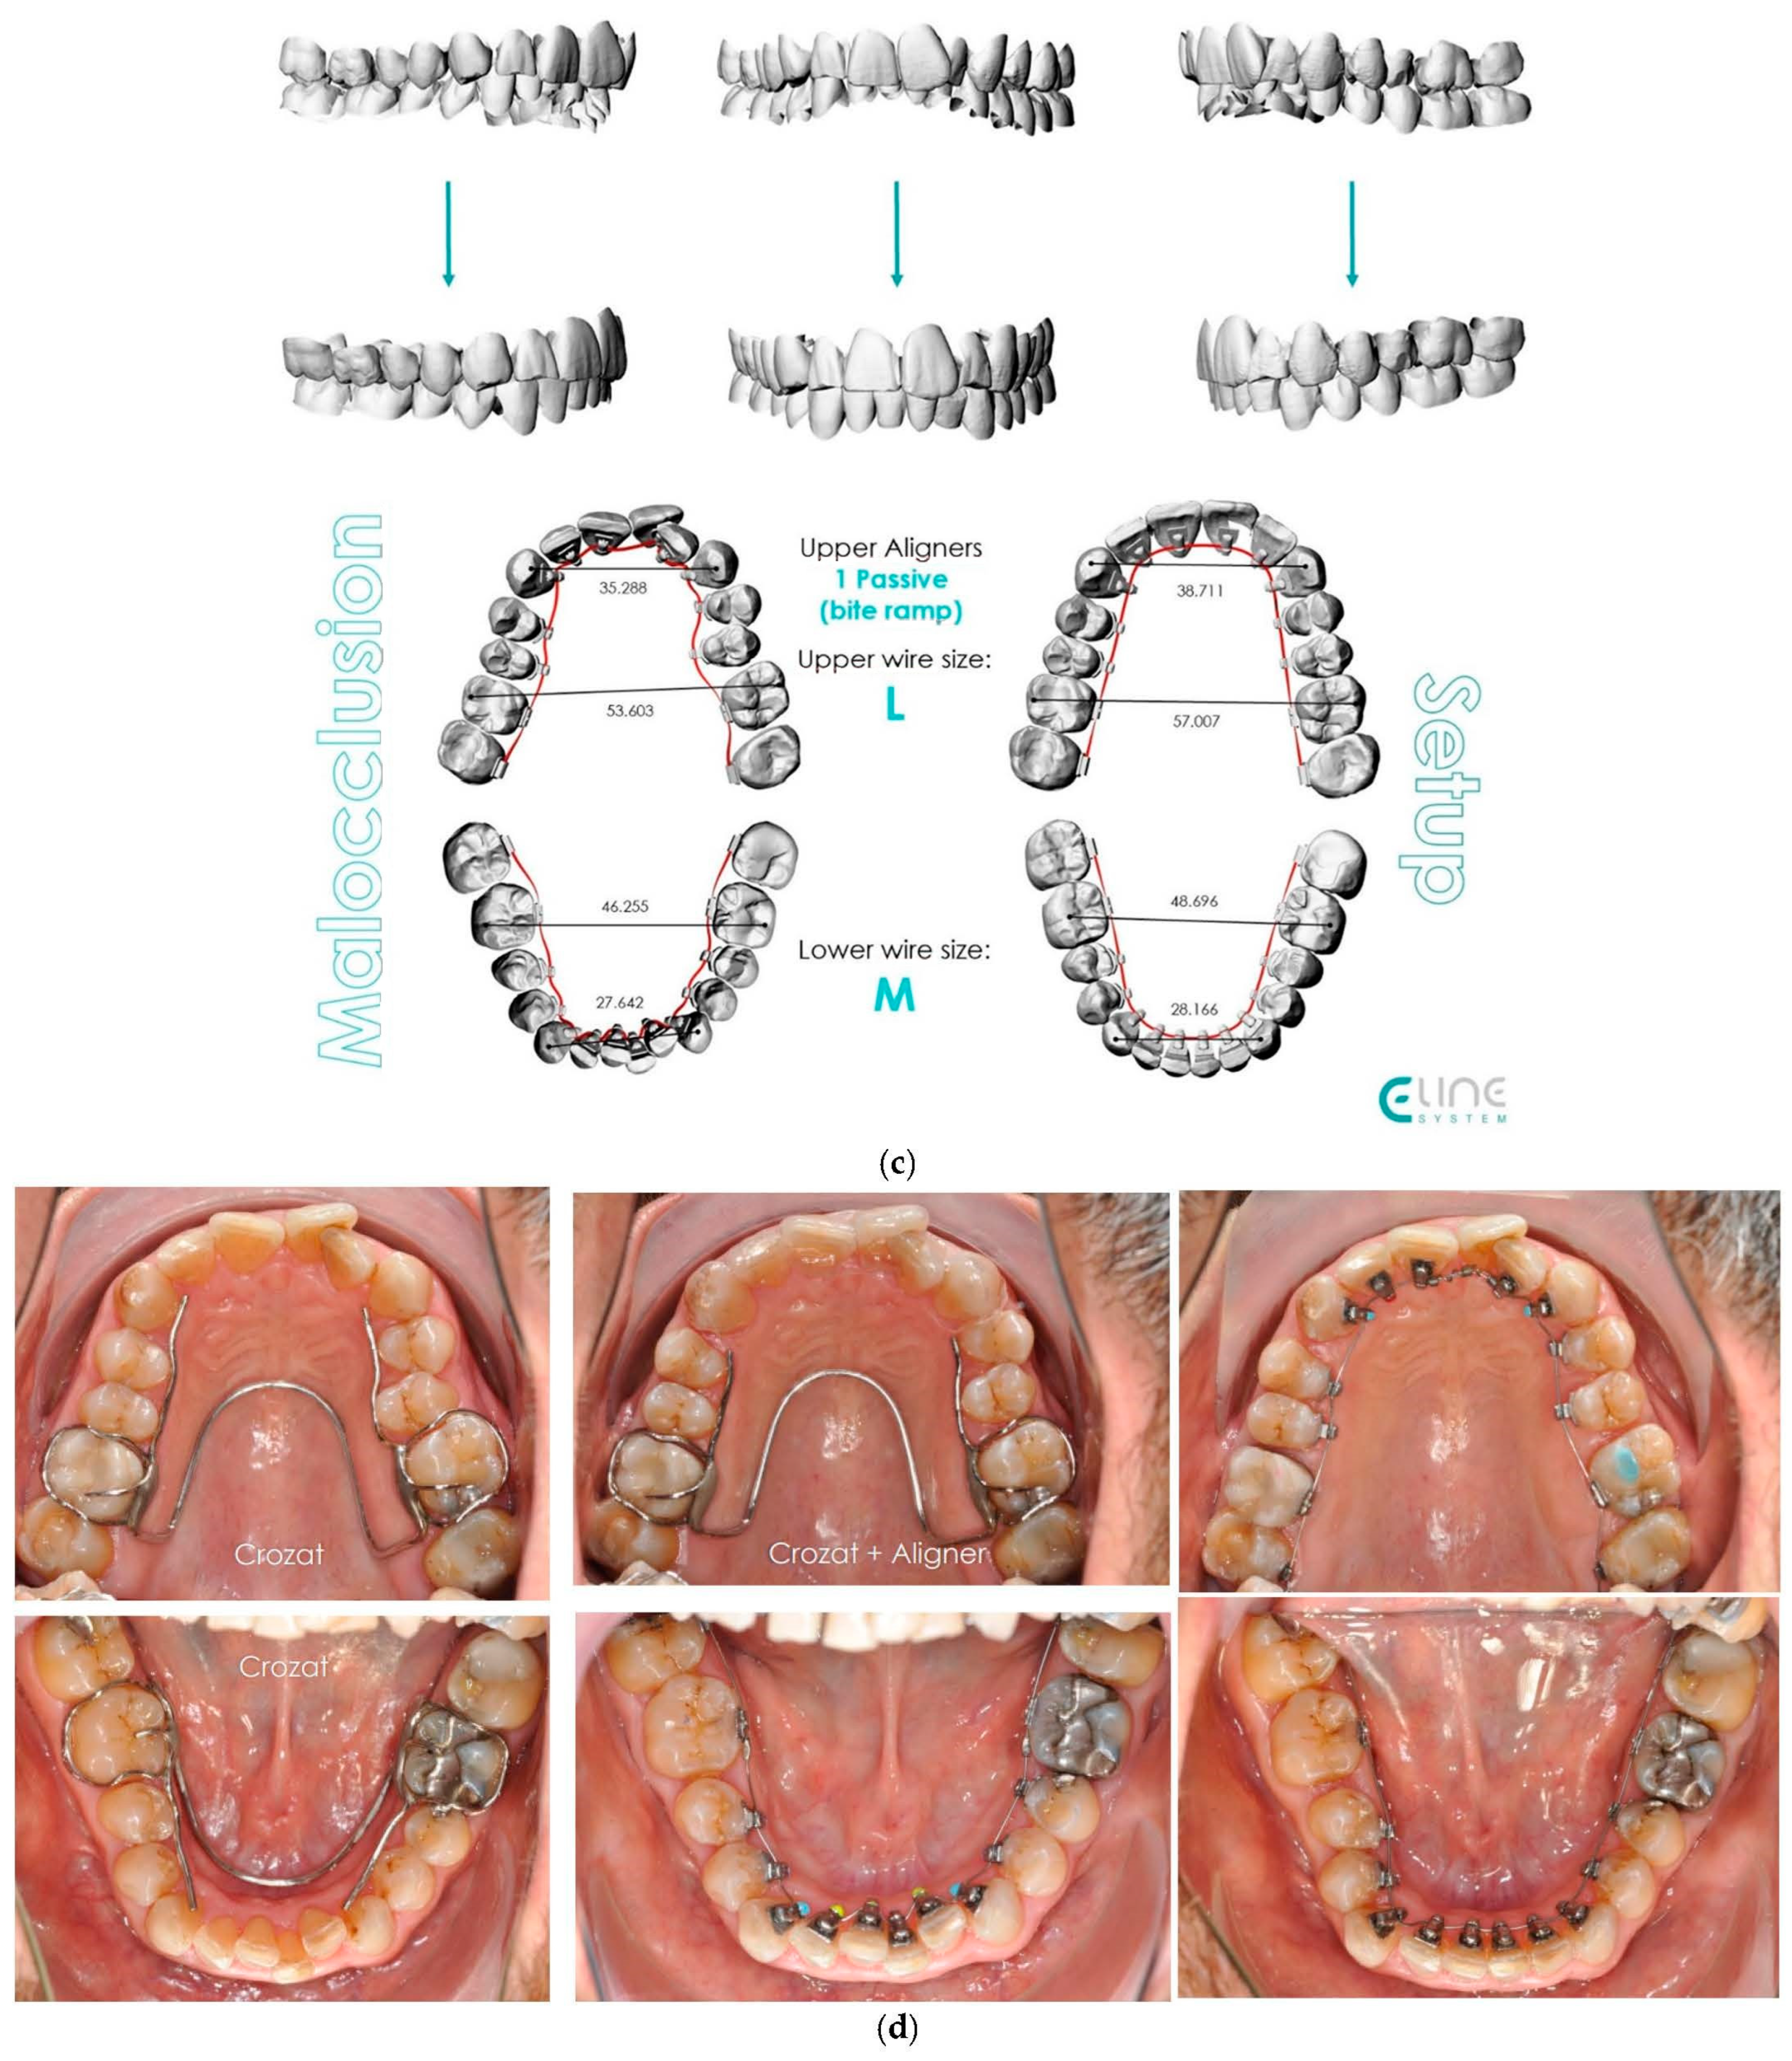

4.1. Case 1: Class II Division 2 with a Deep Bite